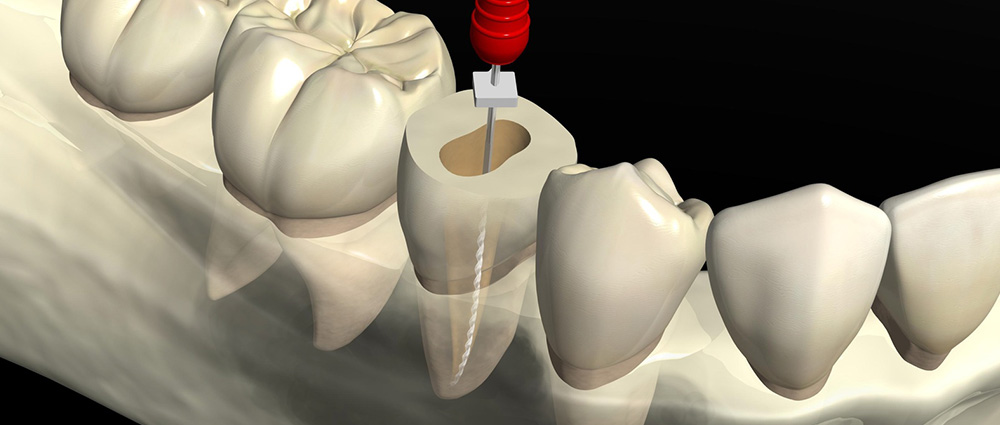

根管治療

歯の根の内部で、神経が通っている管を根管といいます。

細菌が神経にまで到達し、炎症を起こしてしまった場合には、管の中をきれいに清掃し感染物質を除去する必要があります。そのような歯の内部の治療を根管治療と呼びます。

根管治療が必要なケースは、主に虫歯が歯髄(神経・血管)にまで達してしまった場合や過去に神経を除去したにも関わらず、歯の内部が細菌に感染し、膿んでしまった場合などがあげられます。

歯の管はとても細く、また歯によって異なった形をしているため、治療の難易度は非常に高くなります。

もし感染物質をきれいに取り除くことができないと再びそこから細菌が増殖し、膿がたまって腫れたりしてしまいます。

当院では、歯科用CTによる精密な検査と入念なカウンセリングを行い、細心の注意を払って治療にあたっています。虫歯で激しい痛みがあるという場合には、ぜひ一度ご相談ください。